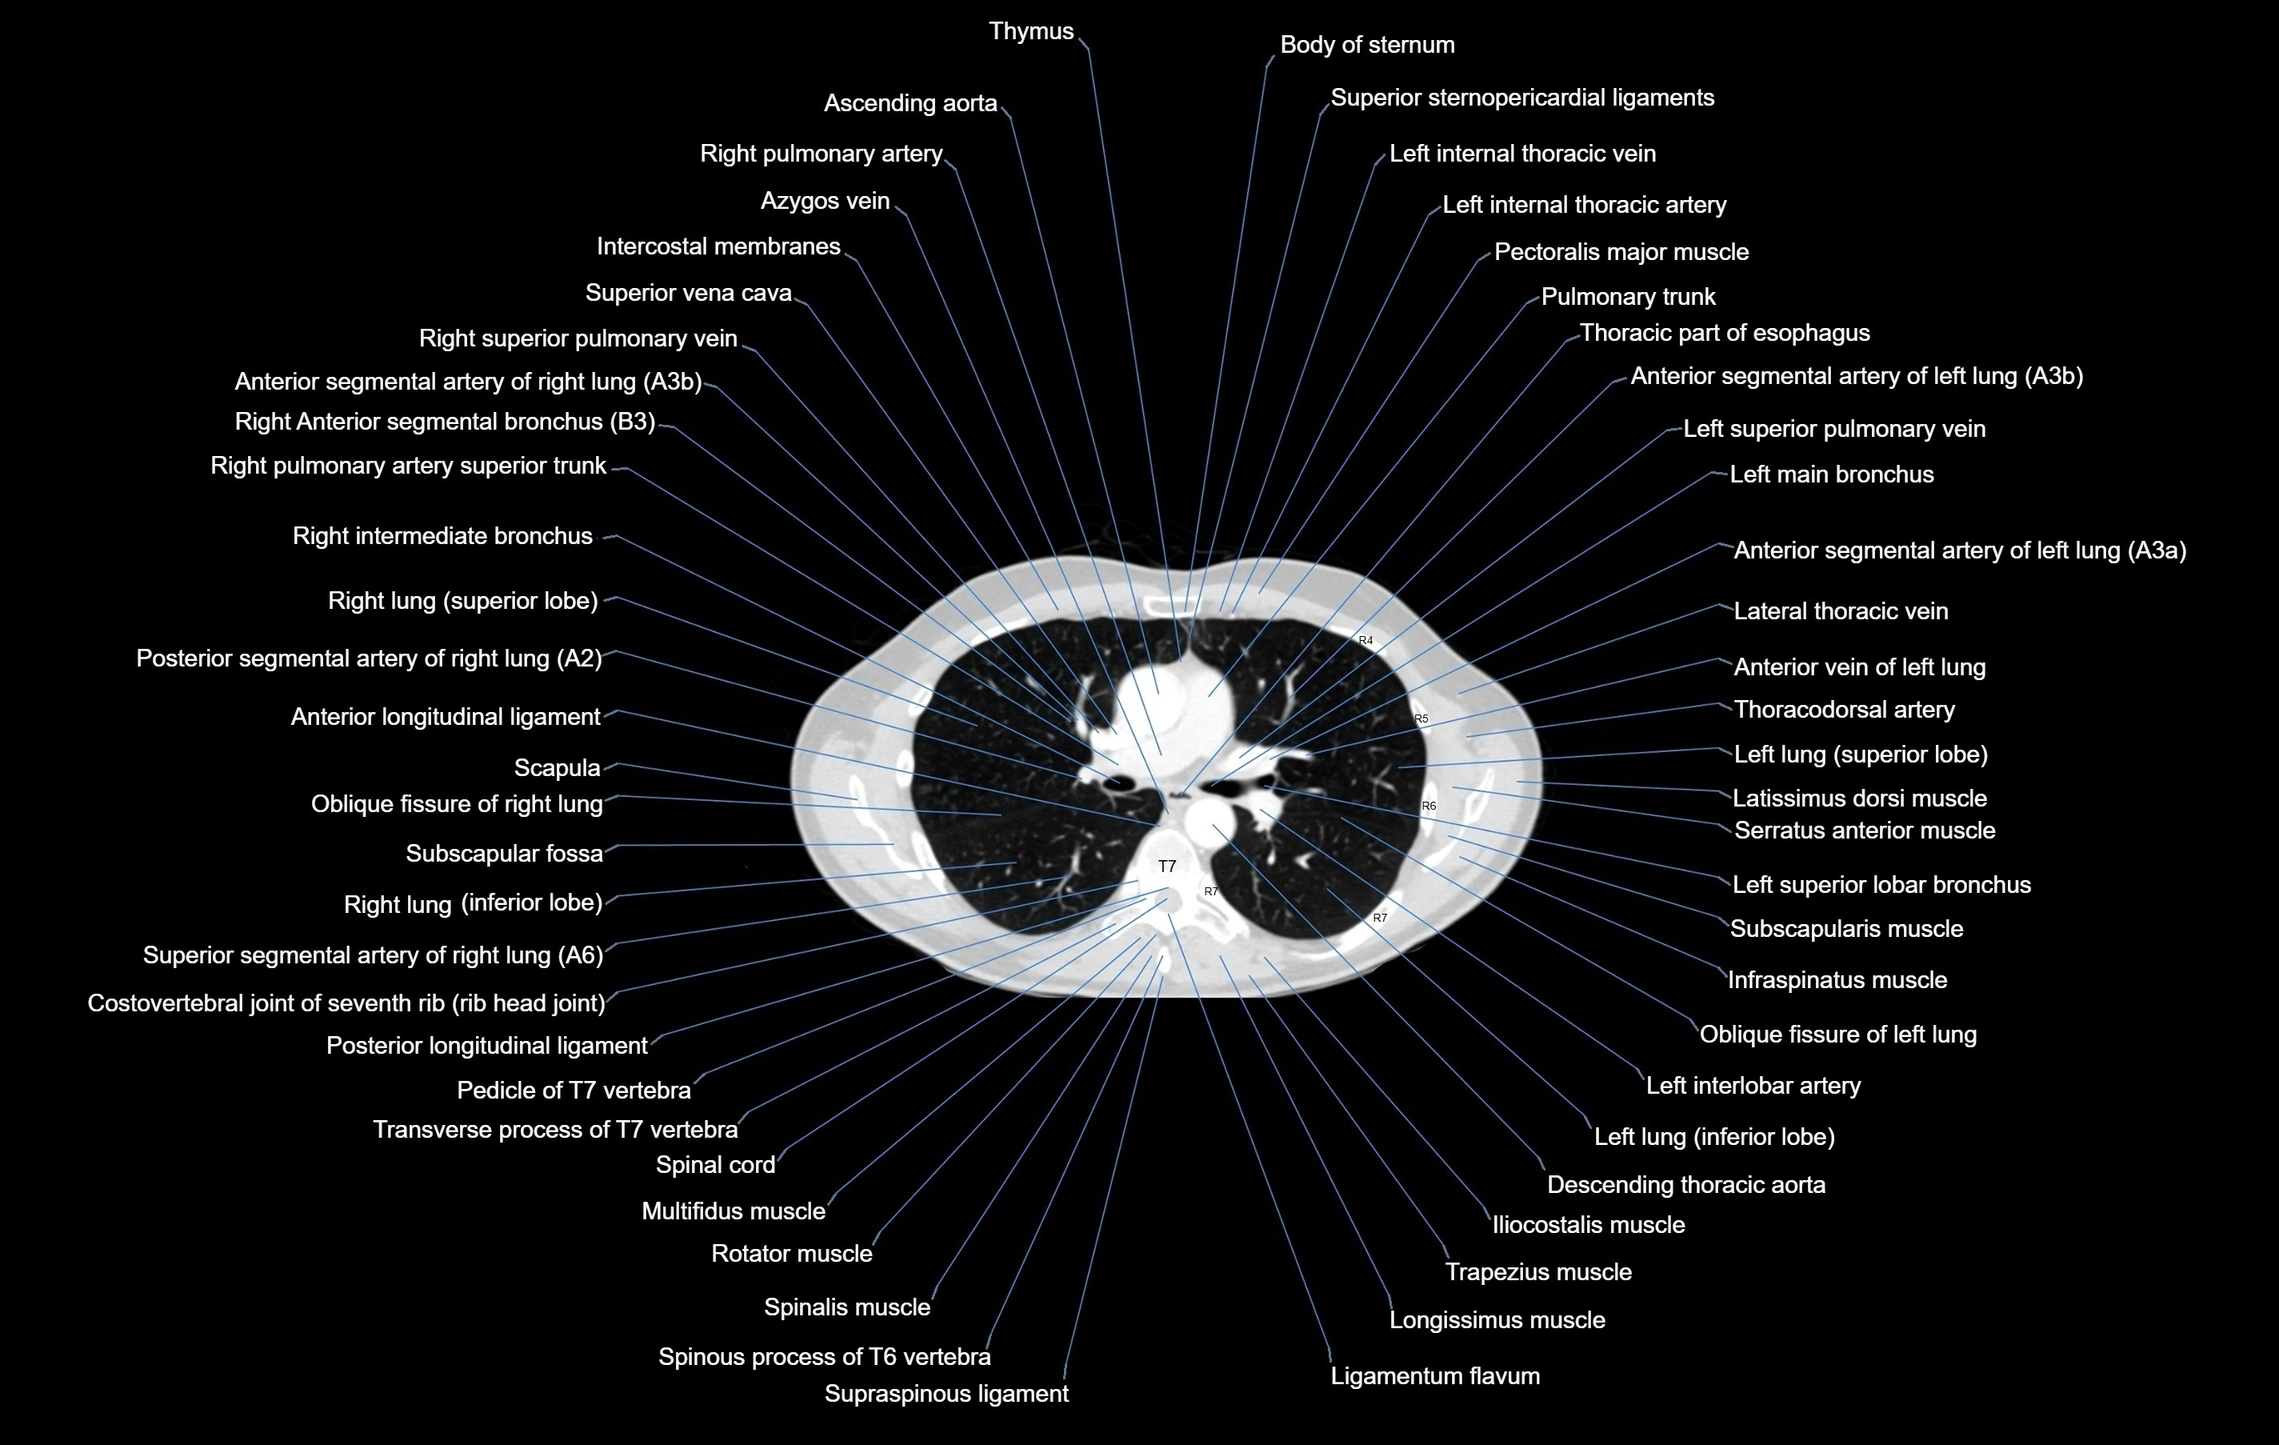

- Ascending aorta

- Azygos vein

- Body of sternum

- Descending thoracic aorta

- Left main bronchus

- Left pulmonary artery

- Left superior pulmonary vein

- Oblique fissure of right lung

- Pulmonary trunk

- Right intermediate bronchus

- Right lung (superior lobe)

- Right pulmonary artery

- Right superior pulmonary vein

- Superior vena cava